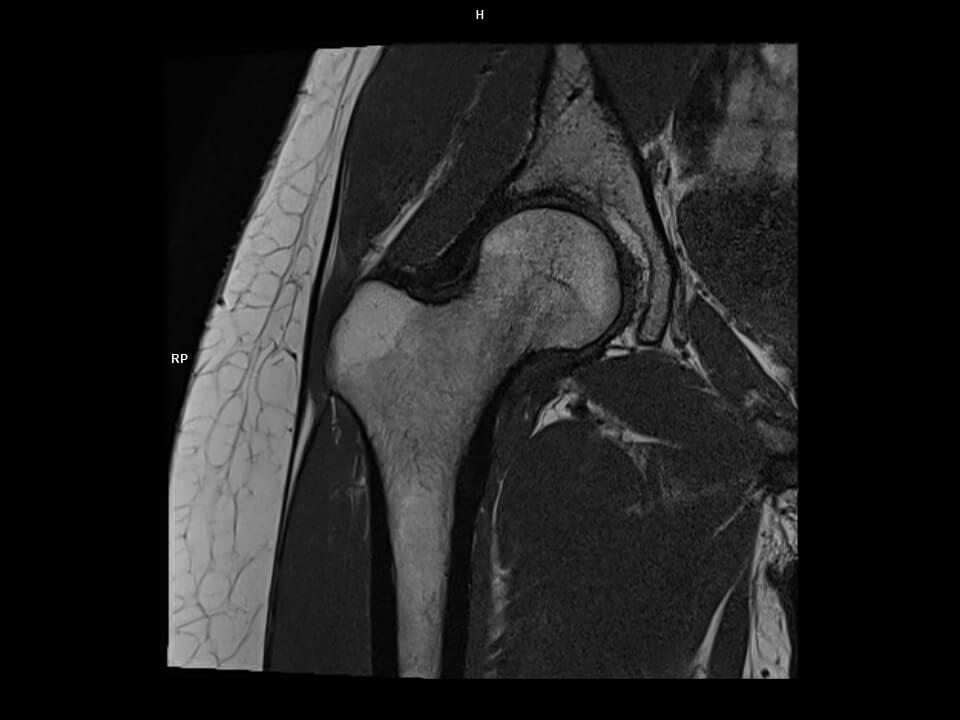

Coronal T1 tse-MAGNETOM Altea

Coronal T1 tse-MAGNETOM Altea/Coil-UltraFlex18 Large/Resolution-416/Scan Time-1:00/Aceleration-s2